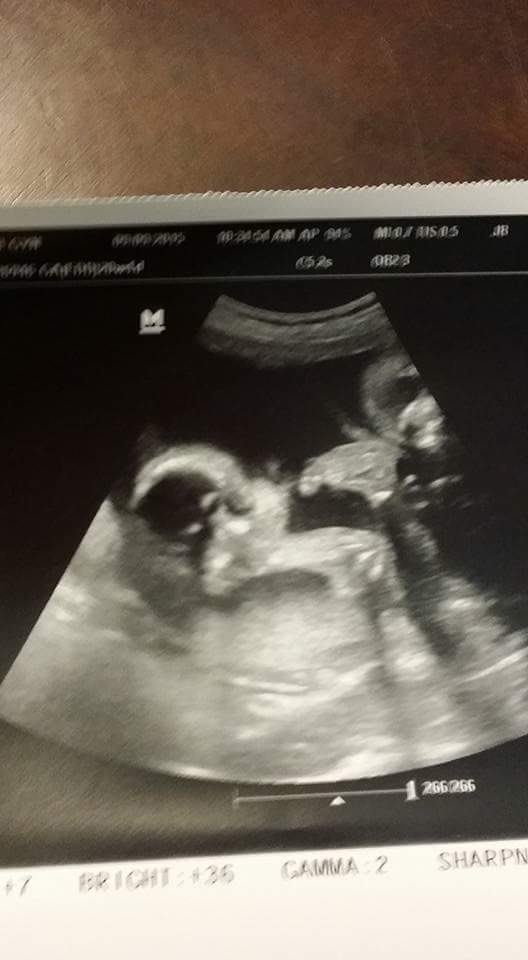

We've had a few OB appointments in between and everything has been great. They were pleased with the results from the anatomy scan and said the twins looked great. We were sent back to MFM for one more follow up appointment. When we went this time, the ultrasound tech had more personality and explained everything. She said she would grade our twins as an A and wished that all the twins were this perfect. Zoey and Kinsley are growing together and neither one of this is too big or too small. Zoey is approximately 1lb 7oz, which puts her in the 53rd percentile, with a heart rate of 139bpm. Kinsley is the chunkier little monkey, measuring approximately 1lb 9oz, 69th percentile, and heart rate of 149bpm. Both of those bright marks were still present on the hearts, but we can know with confidence now that it is nothing to be concerned about since the blood screening came back normal. I walked out of that appointment with a huge smile on my face. My babies are HEALTHY.

On Saturday, we had our 3D/4D ultrasound. It was so neat to have all of our family there to witness it all. Zoey and Kinsley have their daddy's lips and their mommy's chubby cheeks. I've never been into 3D/4D ultrasound but it kind of hits you a different way when it's your own baby/babies. Zoey was a picture hog and didn't want us to get any of Kinsley. She kept putting her hand in Kinsley's face and she had her legs wrapped around Kinsely's neck. They are in two separate sacs so they technically cannot touch each other but pretty close to it. Kinsley's head is right underneath Zoey's chin. They don't have much room in Jade's tiny body but they are making it work. During the ultrasound, they sure were kicking a lot and Jade would blurt out "Ouch". I swear they are going to come out kicking and fighting....I have no clue who they will get that from. HA!

Here are a few pictures from the last few appointments.....

My beautiful baby girls together in one picture

They are both head down